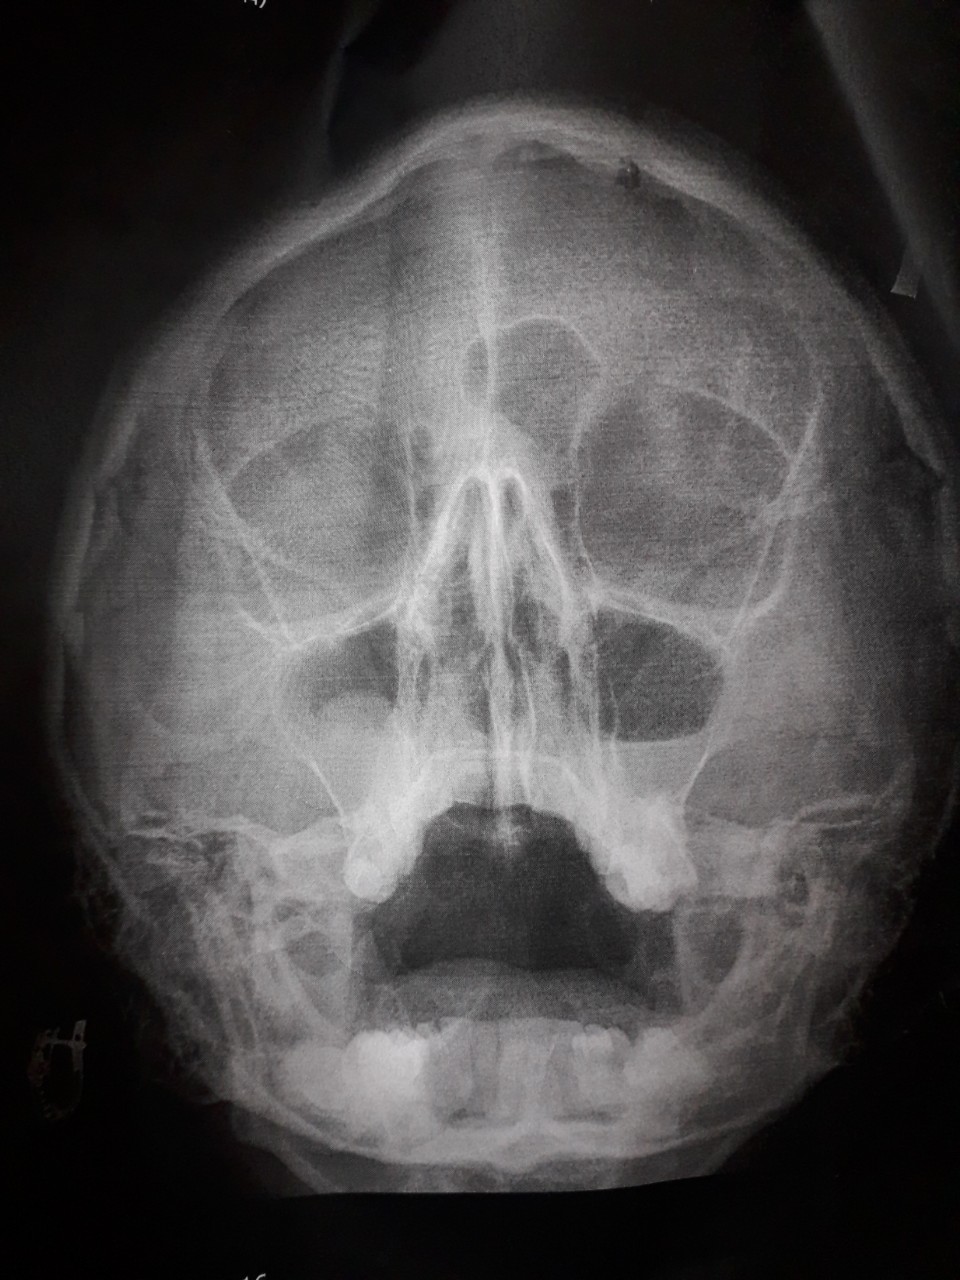

Здравствуйте, очень вас прошу помочь разобраться. У меня киста в правой гайморовой пазухе, я записалась на прием к врачу, который будет мне ее удалять, на 23 апреля. Но 3недели назад у меня стали отекать верхнии веки по утрам, могут и в течении дня отеки появится, если я прилягу. Я сходила к лору в бесплатную полеклинику, мне назначили снимок(фото 1), сказала что у меня острый гаймарит, симптомов никаких кроме насморка не было. Я пропила цетиризин, цефиксим, синупрет и назифрин капала, пришла на прием после лечения, врач снова назначила снимок, и по нему ничего не прошло. Снова назначила лечение цефтриаксон, спрей в нос мометазон, цетрин. И сказала промывать нос изотоническим р-м. Еще у меня сухой небольшой кашель, то есть то нет его. Скажите пожалуйста, могут ли быть отеки у меня из за гаймарита(потому что лор у еоторой я была, молодая девочка, уверяет что нет)? и может ли быть кашель от гаймарита? А то я накрутила себе уже все самое худшее(